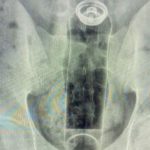

Um jovem de 19 anos, que não teve o nome divulgado, precisou de atendimento médico de urgência depois que um frasco de desodorante ficou preso em seu ânus, na cidade de São Paulo.

O caso foi compartilhado nas redes sociais pelo cirurgião coloproctologista Daniel Brosco, com o objetivo de alertar sobre os perigos de inserir objetos inadequados no corpo durante atividades sexuais. Veja abaixo:

Segundo Brosco, o paciente relatou que o acidente aconteceu durante uma “brincadeira” sexual. O frasco subiu para dentro do reto e, apesar de várias tentativas de remoção em casa, foi necessário buscar ajuda profissional.

O médico explicou ainda que os movimentos naturais do intestino e o vácuo criado na região dificultam a retirada manual de objetos estranhos.